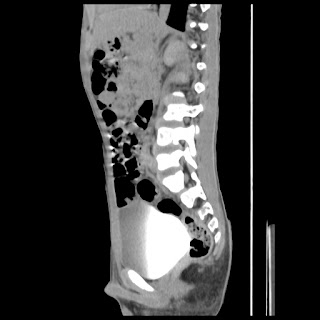

A 07 years old child with left side of abdomen pain

current CT images: